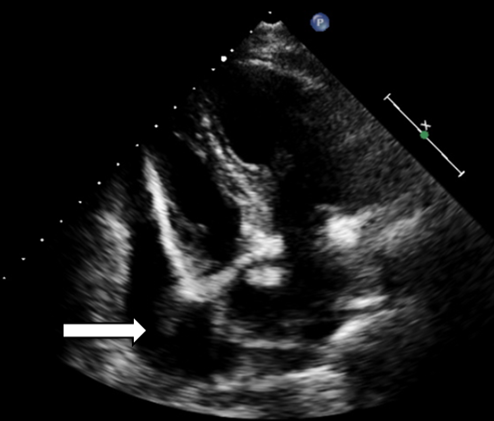

Posteroanterior chest radiograph showed cardiomegaly without any lung lesion. (Figure 1) An emergent ECHO cardiogram showed moderate Pericardial effusion (posteriorly 17mm, anteriorly 4mm, laterally 6mm) There was no RA/RV diastolic collapse seen. (Figure 2)

Figure 2: Transthoracic echo showing pericardial effusion. (white arrow)